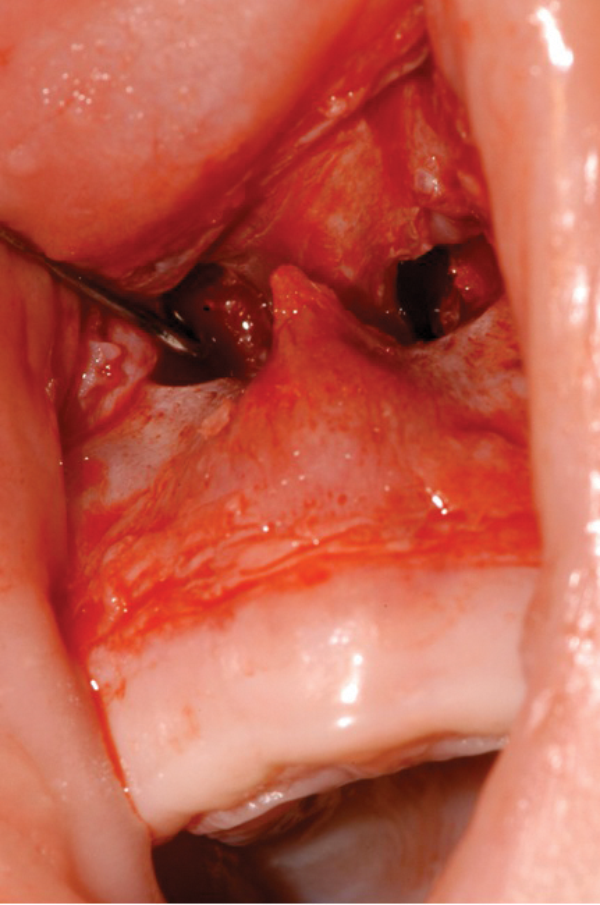

Figure 2: The stenosed pyriform aperture is approached through a sublabial incision.

- The stenosed pyriform aperture is approached through a sublabial incision (Figure 2).